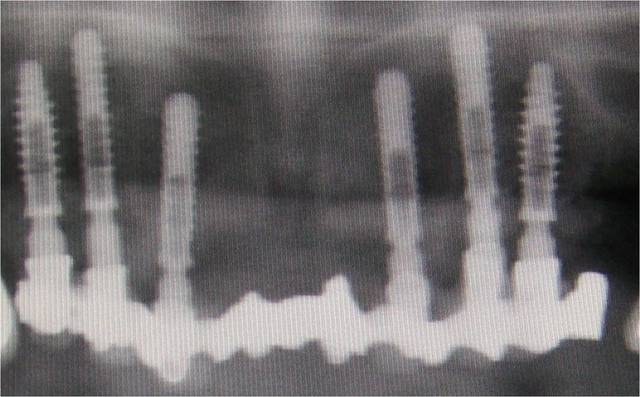

Pour être précis je dirais que l'implant en 27 et non pas 26 n'a jamais été vraiment bien

Mais parle moi donc plutôt du résultat en 46 47 qui sont dans la même bouche avec le même terrain paro

Simple question, pourquoi conserver les dents postérieures (28-38, je pense) qui sont en phase finale de paro ?

L'implant 27 devrait aussi être remplacé, enfin, selon ce qu'on voit sur les images montrées.

Il y avait 9 implants avant la chir 1 va mal et tous vous focalisé, amusant mais classique

28 n'est pas en rapport avec le problème de l'implant 27

Dans 3 mois 28 & 38 vont disparaitre, et je tenterais en même temps de sauver 27

En cas d'échec probable dans l'implant disparaitra et lors de la prothèse définitive j’intégrerais 26 ou pas